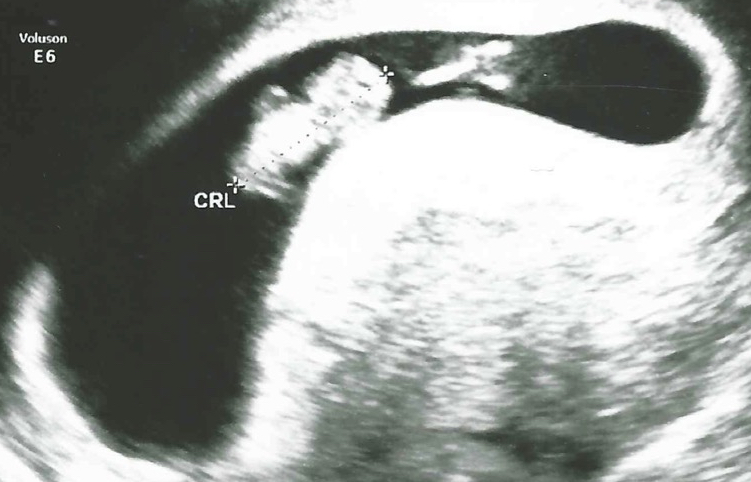

8 weken

Een echo na 8 weken.